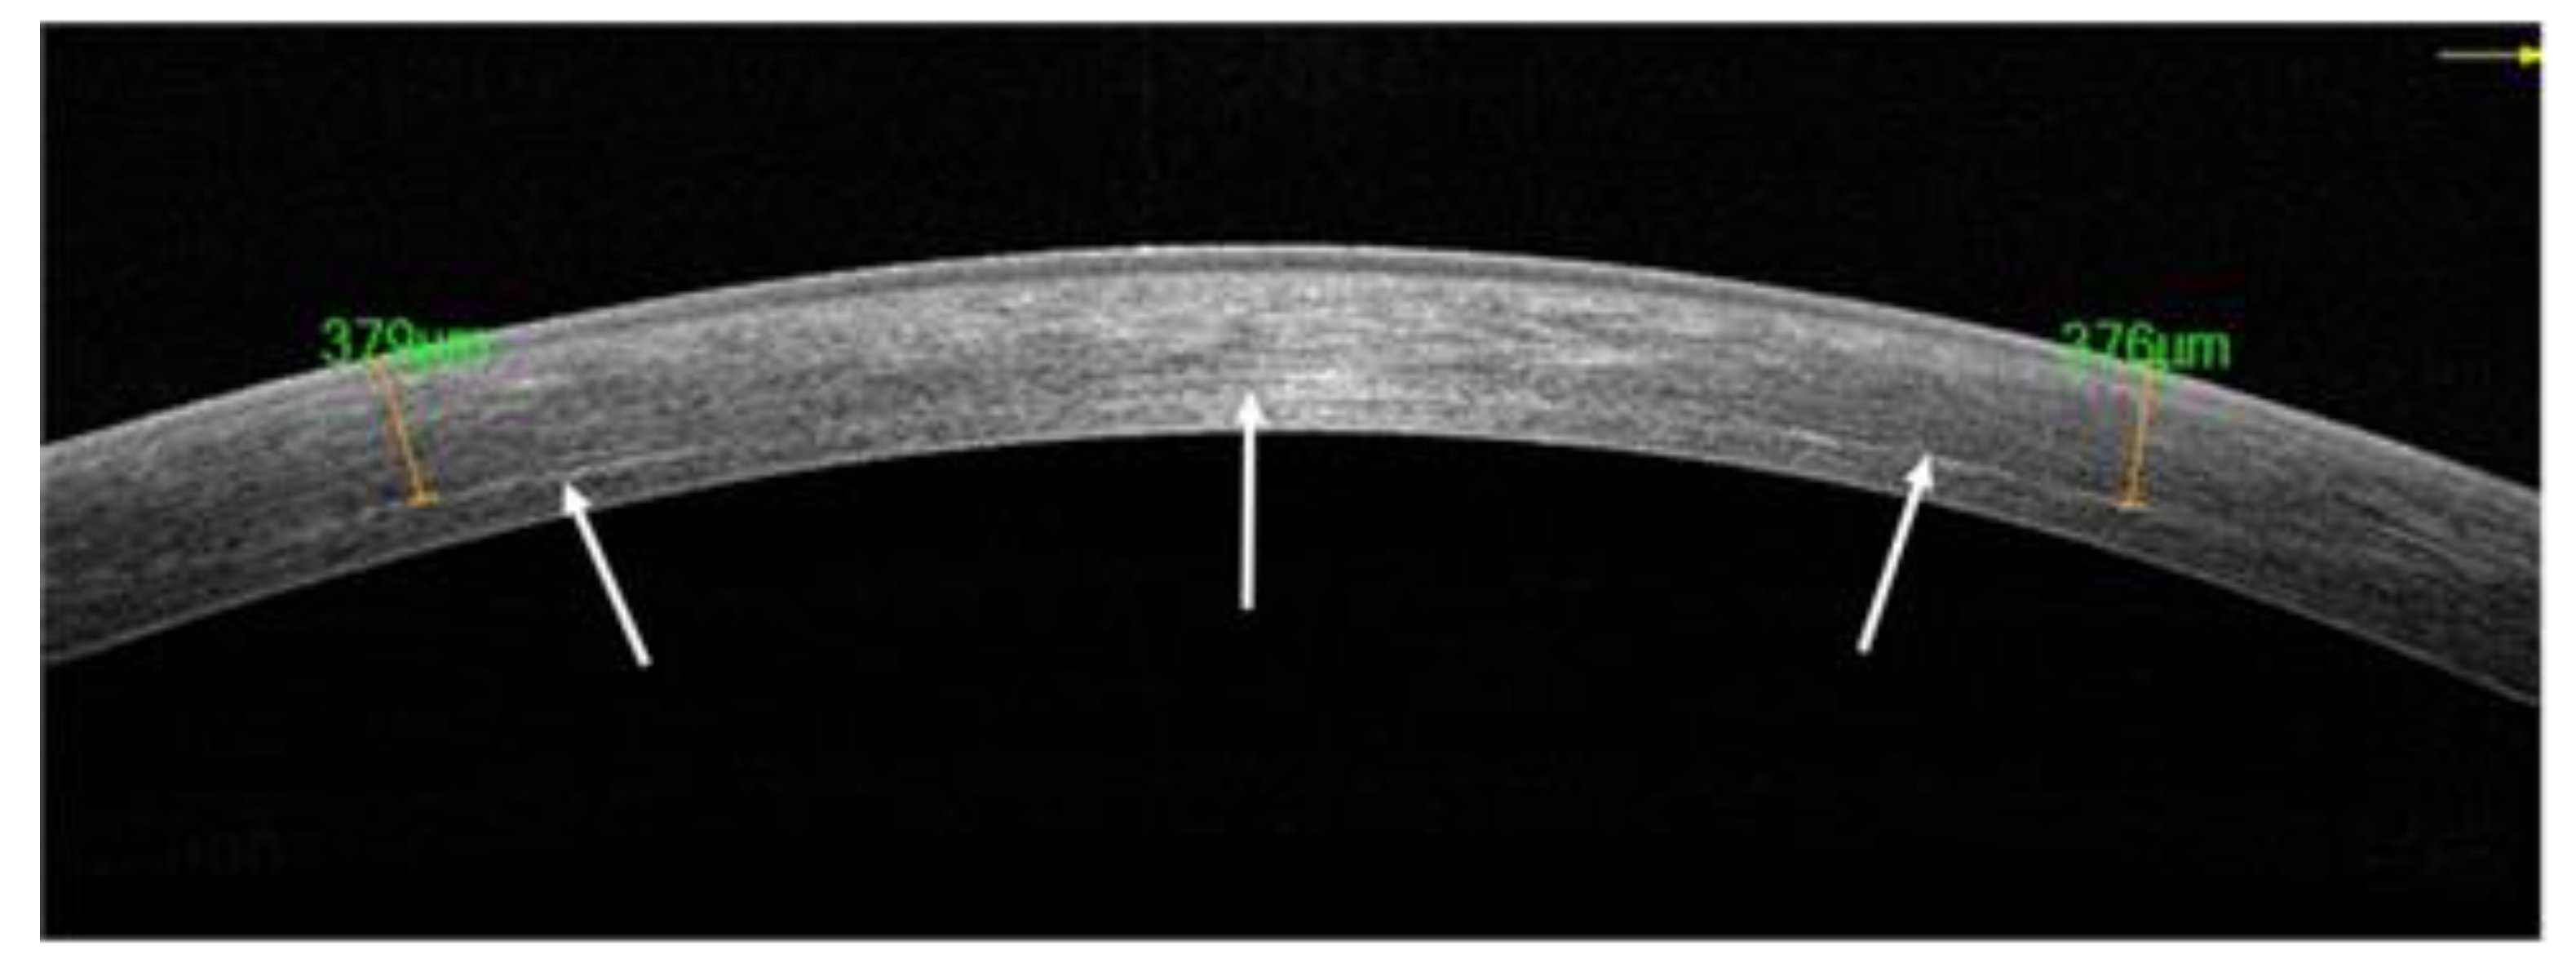

| Eyes (n = 10) | Demarcation Line Depth (µm) 1 m Postoperative (with Epithelium In Situ) | ECD Baseline Cells/mm2 | ECD 1 m Postoperative Cells/mm2 | ECD 6 m Postoperative Cells/mm2 |

|---|---|---|---|---|

| 1 | 376 | 2042 | 2012 | 2133 |

| 2 | 329 | 2155 | 2112 | 2089 |

| 3 | 379 | 2332 | 2188 | 2234 |

| 4 | 330 | 2578 | 2490 | 2502 |

| 5 | 367 | 2627 | 2500 | 2599 |

| 6 | 362 | 2244 | 2321 | 2444 |

| 7 | 338 | 2188 | 1987 | 2112 |

| 8 | 342 | 2277 | 2222 | 2189 |

| 9 | 355 | 2289 | 2223 | 2301 |

| 10 | 380 | 2692 | 2497 | 2560 |

| AVG | 355.8 | 2342 | 2252 | 2316 (p > 0.05) |